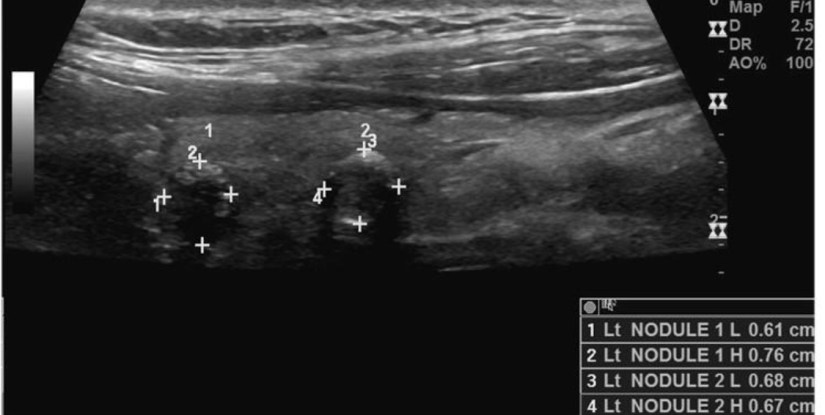

👉Thyroid cancers less than 1 cm in size are called “microcarcinomas”.